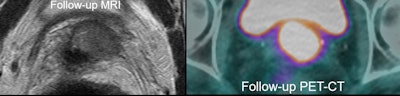

33-year-old LACC patient with stage 2B disease, node negative. MRI was performed 86 days after completion of conformal radiation therapy. Score grade 1 was recorded, indicating complete response. All images courtesy of Prof. Andy Scarsbrook.

33-year-old LACC patient with stage 2B disease, node negative. MRI was performed 86 days after completion of conformal radiation therapy. Score grade 1 was recorded, indicating complete response. All images courtesy of Prof. Andy Scarsbrook. FDG-PET/CT in the same patient shows primary tumor, SUVmax 11.5. FDG-PET/CT scan performed 94 days after completion of CRT gave score of grade 4, indicating patient metabolic response.

FDG-PET/CT in the same patient shows primary tumor, SUVmax 11.5. FDG-PET/CT scan performed 94 days after completion of CRT gave score of grade 4, indicating patient metabolic response. MRI performed five months later showed local relapse. PET/CT confirmed this and showed no distant disease. Patient underwent salvage pelvic exenteration and was disease-free two years later.

MRI performed five months later showed local relapse. PET/CT confirmed this and showed no distant disease. Patient underwent salvage pelvic exenteration and was disease-free two years later.A total of 95 patients were included in the study. Of these, 21 (22%) had evidence of persistent local and/or nodal disease after CRT. The diagnostic performance of MRI (accuracy 77%, positive predictive value [PPV] 29%, negative predictive value [NPV] 84%) and PET/CT (accuracy 77%, PPV 27%, NPV 94%) was similar.